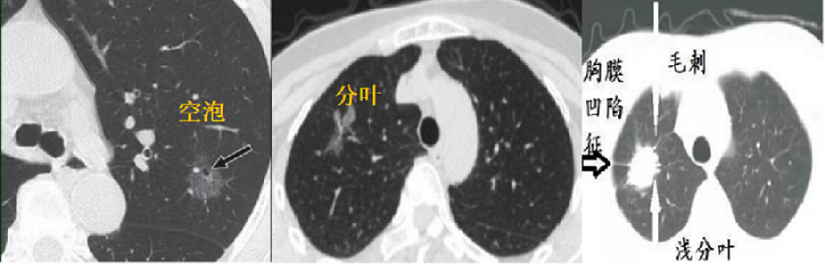

第一种,具有明显恶性征象的肺结节

像下图这种,出现胸膜牵拉、分叶、毛刺 等表现要及时手术。